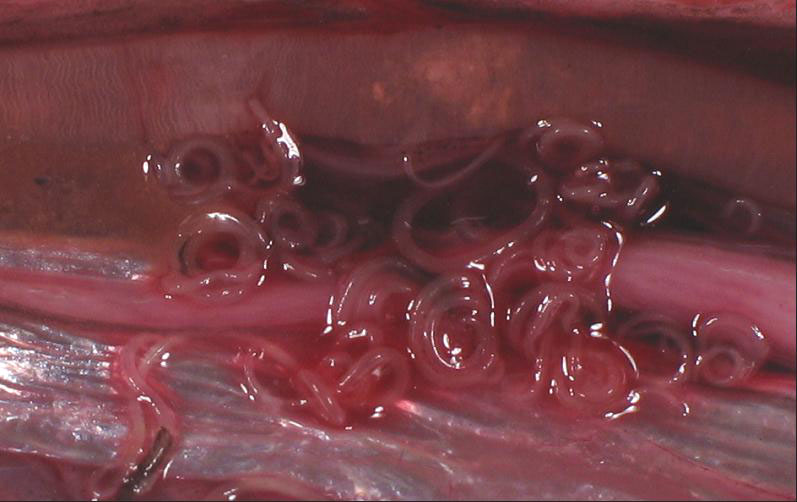

L’anisakis è un nematode (verme) parassita che si annida nelle pareti dello stomaco. Il pesce e i crostacei sono le principali fonti di contagio: l’uomo mangiando pesci, o calamari crudi o poco cotti, può ingerire le larve dei nematodi, responsabili di una malattia nota come anisakidiosi. Le larve ingerite spesso muoiono o non danno sintomi. In alcuni casi però possono invadere la mucosa gastrica o intestinale e causare dolori addominali, nausea, vomito ed occasionalmente febbre. Una volta penetrate nella mucosa ne deriva una reazione infiammatoria che può evolvere fino a causare ulcere (fonte: IZS Veneto).